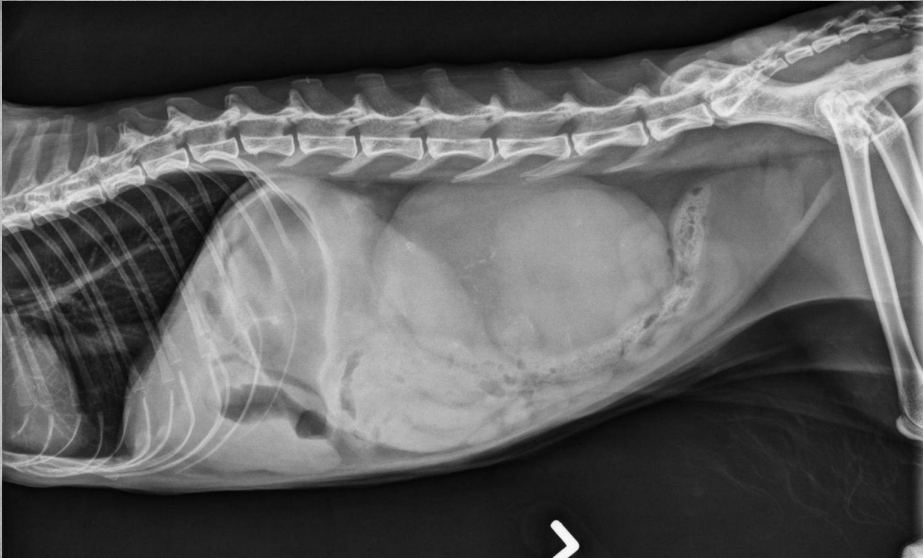

●9 yo female sterilized German

Shepherd

●Anorexia, lethargy

●Weakness

● Mass effect, bowels lifted dorsally

and caudally

● Round shadow cranially to tail of

the spleen

● Splenomegaly, splenic mass. hemangiosarcoma